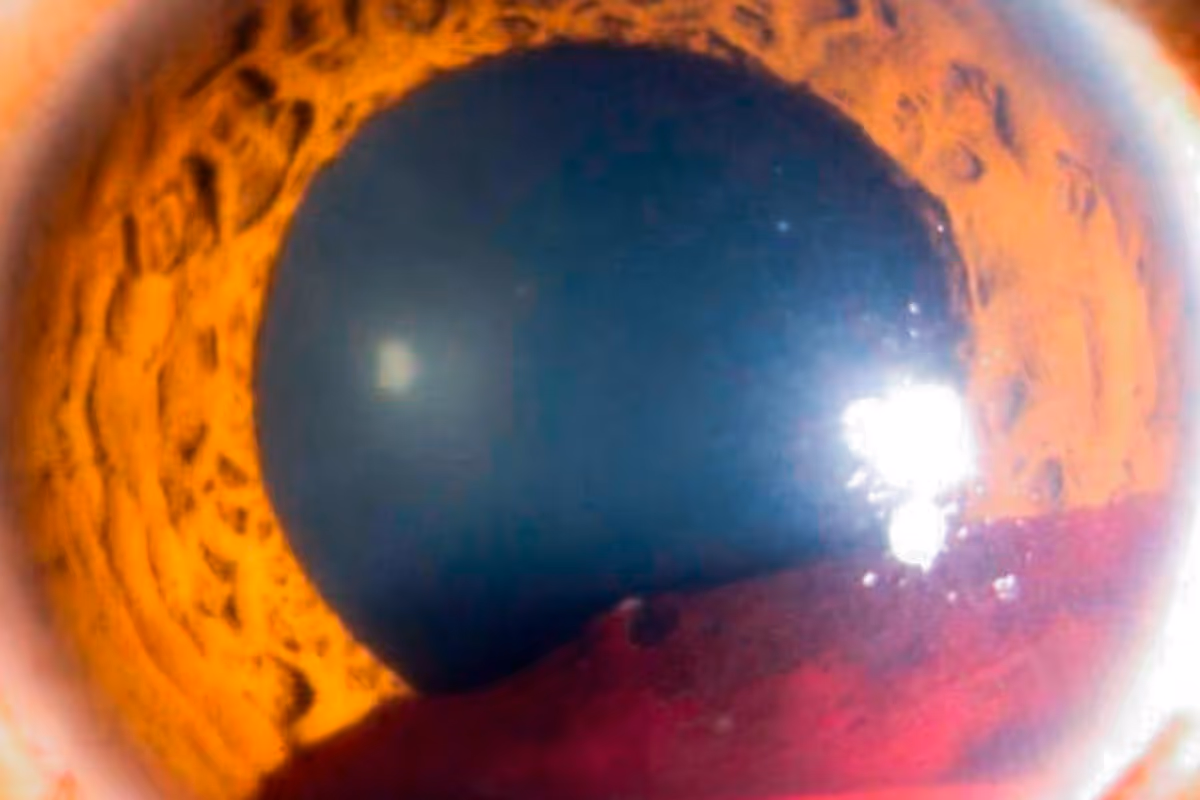

Edema de papila: es la inflamación de la cabeza del nervio óptico (parte visible del nervio en la retina), puede ser causado por inflamación, isquemia, traumatismo, infección del nervio óptico o aumento de la presión interior del cerebro a consecuencia de tumores, meningitis o encefalitis.

- Angiografía con fluoresceína y fotografía de fondo de ojo: a través del servicio de imagenología se obtienen fotografías de fondo de ojo para observar el nervio óptico, la retina y la mácula. El procedimiento se realiza de lunes a viernes de 8:00 a 15:00 horas, consiste en dilatar la pupila para obtener imágenes con equipo especializado